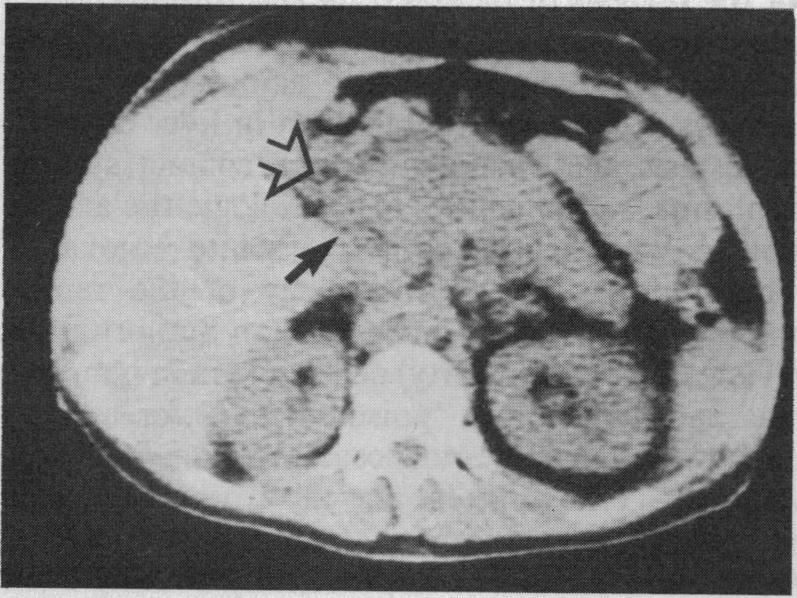

Papadimitriou J, Fotopoulos A, Exarchacos G

J R Soc Med. 1980 Sep;73(9):681-2.